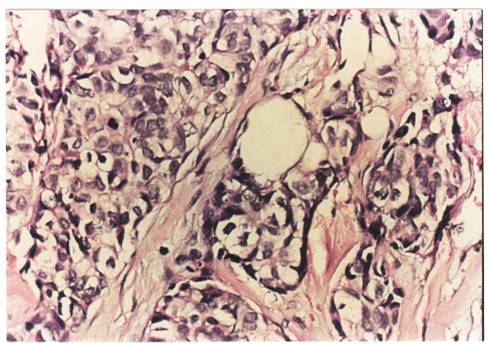

Criterii microscopice de diagnosticare a cancerului mamar

Pentru examenul histopatologic piesele de mamectomie sunt prelucrate prin imparafinare si colorate cu Hematoxilina-Eozina sau, pentru observarea mai buna a tesutului conjunctiv, cu Van Gieson.

Colorarea se realizeaza pentru observarea difertiata a structurilor celulare (colorantul adera selectiv la structurile celulare, colorandu-le diferit). Hematoxilin-eozina contine hematoxilina si eozina (colorant acid anionic). Colorantul se oxideaza la aer in timp indelungat sau chimic, cu iodura de sodiu. Colorantul determina culoarea roz a citoplasmei celulare, nucleul bazofil (albastru-violet), heterocromatina se coloreaza intens, dar nu si invelisul nuclear, nucleolii apar foarte colorati si in citoplasma se observa granule albastru- violacee, ce sunt ribozomii, care contin ARN.

Pe preparate colorate, la microscopul optic se observa urmatoarele imagini :